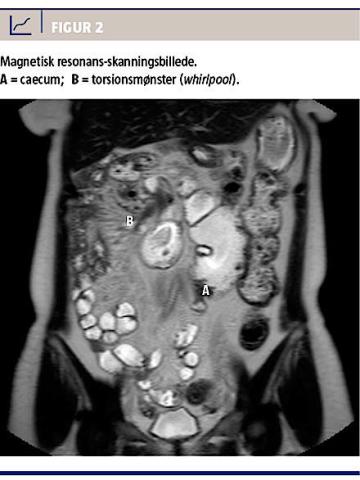

En ultralydskanning af øvre abdomen viste normale forhold. På baggrund af en colonindhældning foretaget 13 år tidligere blev der rejst mistanke om malrotation. Efterfølgende MR-skanning og computertomografi (CT) viste malroteret colon med caecum placeret til venstre for midtlinjen i umbilikalniveau. Skanningen viste desuden torsionsmønster i tyndtarmskrøset beliggende i højre øvre kvadrant, vægfortykkelse af duodenum og inflammation i krøset i det torkverede område (Figur 2). Patienten blev efterfølgende indkaldt til laparoskopisk deling af de laddske bånd, hvor man verificerede diagnosen. Der blev foretaget deling af et langstrakt fladt bånd mellem colon ascendens/caecum og duodenum/lever/laterale bugvæg samt detorkvering af mesenteriet. Operationen forløb planmæssigt med et ukompliceret postoperativt forløb.